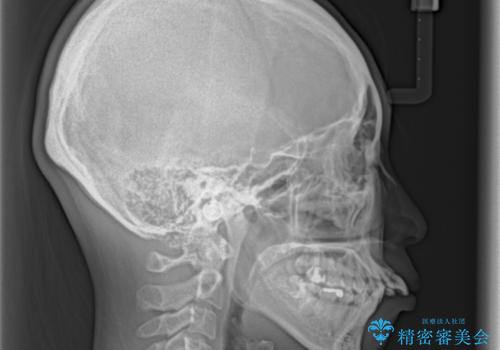

- 口元がひどく突出するくらいの上顎前突を気にして来院された患者様です。

舌の突出癖が顕著で、上顎歯列は完全なV字型となっている状態でした。

下顎歯列にも八重歯があり、上下左右の第一小臼歯4本を抜歯して、ワイヤー装置にて矯正治療を行うこととしました。

どこまで口元の突出感を改善できるのか不安でしたが、舌のトレーニングをしっかりと行ってくださり、我々も驚くほど劇的に改善することができました。